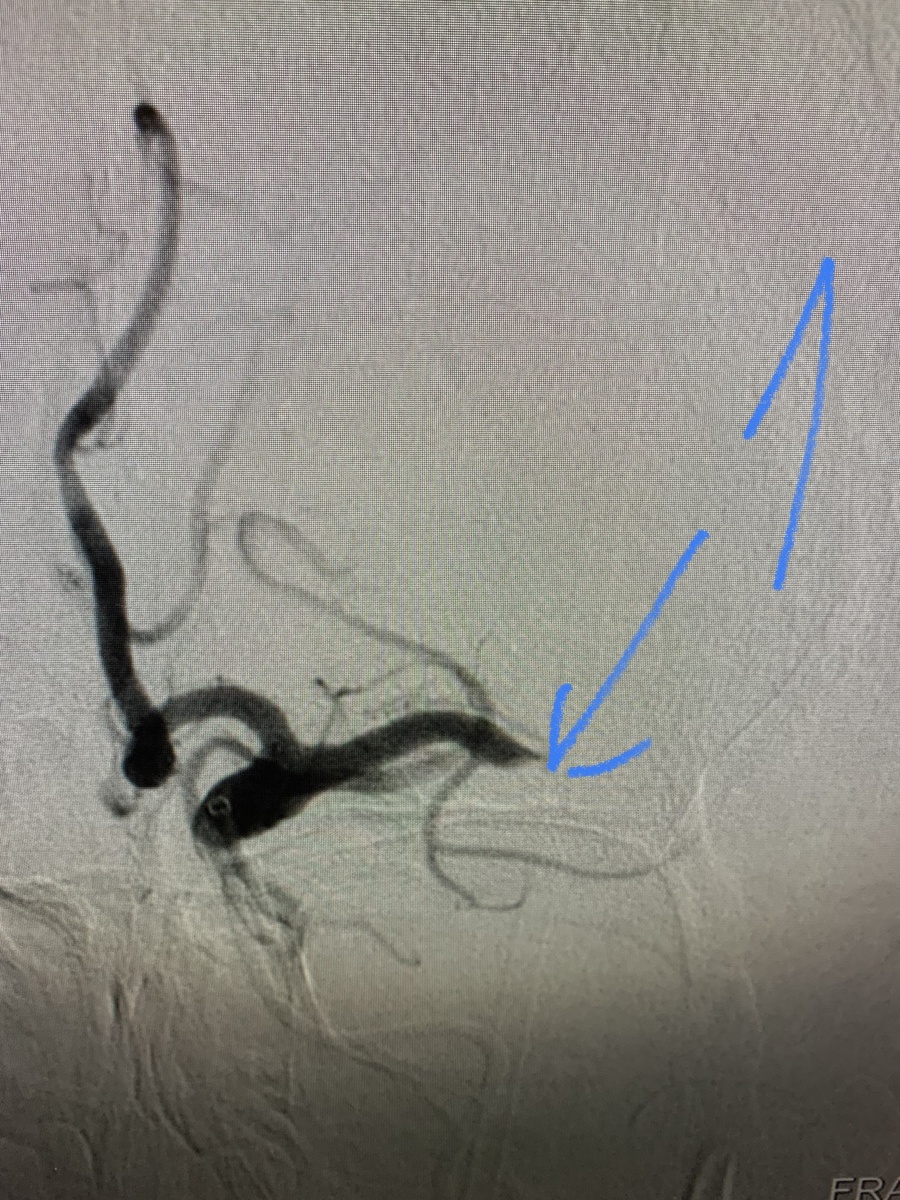

Говорят, что в этой группе одни ужасы и инфаркты. Поэтому вот вам история с инсультом и счастливым концом! В картинках, конечно. 1. Средняя мозговая артерия с тромбом. 2. А теперь она течет. 3. Аспирационный катетер Sofia, придуманный для заползания через все извитости внутренней сонной артерии далеко в голову.4. Тромб, который пытался превратить нашу пациентку в парализованного инвалида, но не смог. 5. Ольга Симонова - эндоваскулярный хирург, и анестезиолог Алексей Бельков, которые смогли в Елизаветинской больнице удалить тромб из средней мозговой артерии и вылечили пациентку с инсультом. Хотите чтоб Ольга с Софией забралась и в Вашу среднюю мозговую? тогда есть 3 совета: 1. Никаких статинов с высоким холестерином. 2. Высокое давление - дело житейское и таблеток не требует. А главное: 3. при мерцательной аритмии не принимать антикоагулянты. Будьте здоровы и берегите себя! PS и пожалуйста, знайте симптомы инсульта